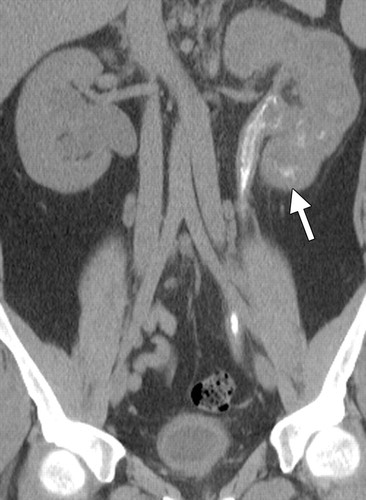

SPOTTED NEPHROGRAM

Figure 5A

A late arterial phase from an aorto- gram shows bilateral spotted neph- rognams in a patient with polyartenitis nodosa.

Figure 5B

This is a late phase from a selective renal arteniogram in the same patient; it demonstrates occlusion of multiple peripheral vessels with cortical irregu- lanity.